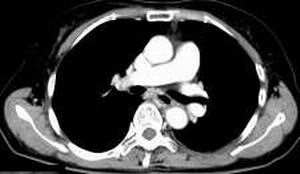

女,61岁,吞咽困难(包括开水)已久。

食道中上段癌并锁骨上窝淋巴结转移.

1、同意食道上段ca併淋巴结转移。

2、做食道呑钡就一目了然。

3、右侧甲状腺是否有问题?是否甲状腺ca转移食道上段。因为肿块顶部图像没有,请楼主展示,谢谢!

食道中上段中分化鳞癌伴锁骨上淋巴结转移

大家都很正确,谢谢!